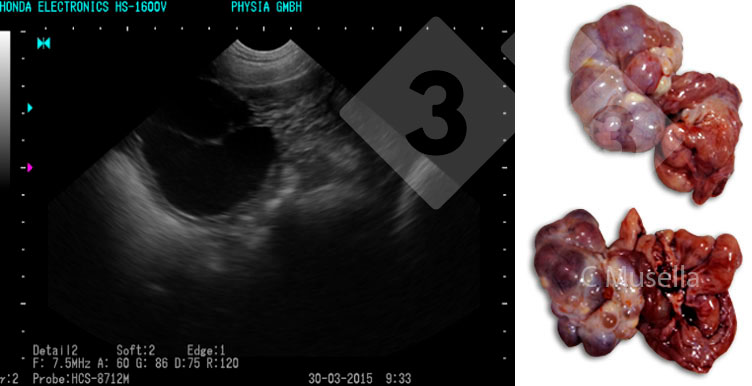

Rozpoznanie pojedynczych lub mnogich torbieli jajnika jest stosunkowo proste, nawet jeśli pełna identyfikacja typu torbieli na podstawie obrazu USG nie zawsze jest pewna.

Jeśli chodzi o struktury macicy, obecność płynu, nie będącą wynikiem ciąży, nasienia lub rui, należy uznać za patologiczną i wskazującą na wysiękowe zapalenie macicy. Obserwacja wysięku za pomocą ultradźwięków jest możliwa tylko wtedy, gdy stan zapalny jest ostry.